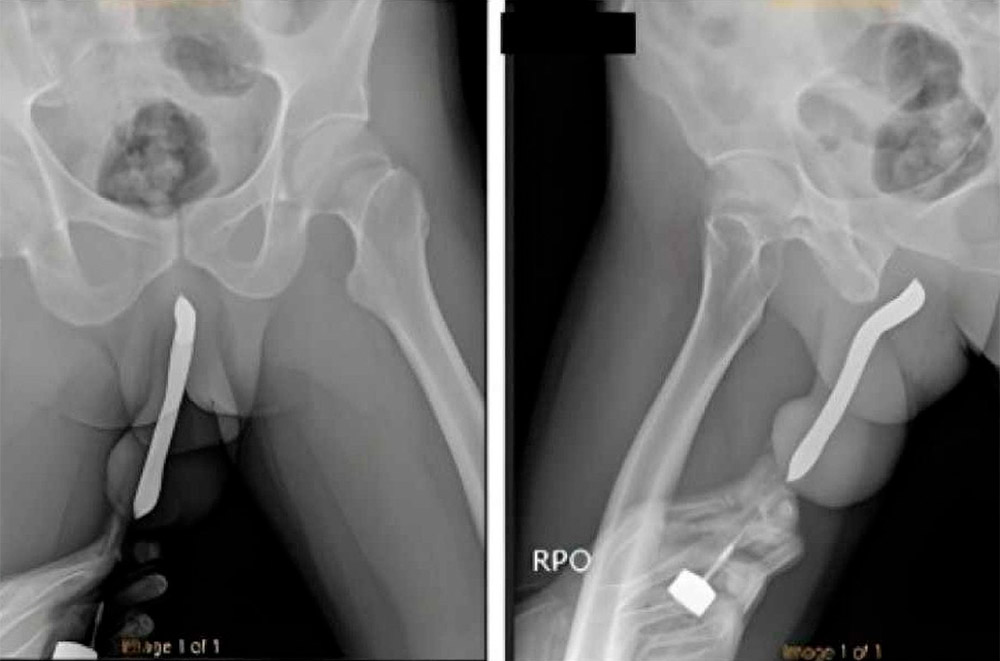

Há quem goste de um prazer extremo e o uso de itens cotidianos, ao invés do sexo convencional e dos toys. Uma prática muito vista no pornô gay é a colocação de itens na uretra, geralmente para uma punheta rápida. No entanto, um homem não identificado de 43 anos foi além, ele costumava colocar uma escova de dente na uretra para deixar o pau ainda mais rígido, depois transava normalmente. Em uma das sessões de "escovação", a escova de dente quebrou e ele teve que passar por uma longa cirurgia.